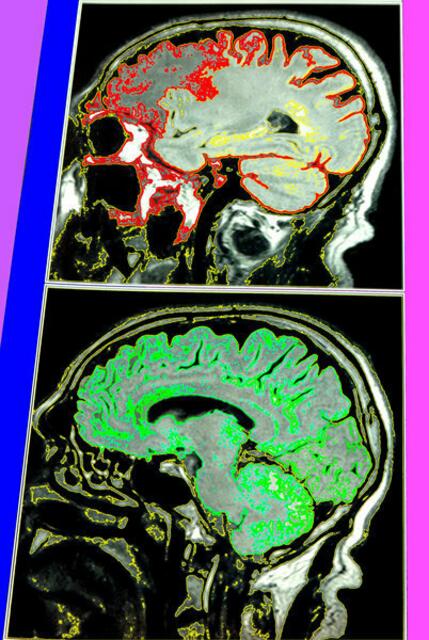

Für die Entstehung der Symptome der Parkinson-Krankheit sind die Nervenzellen der Substantia nigra (schwarze Substanz) von besonderer Bedeutung. ... Mittelhirn-a&s-p-malerei. wh

Für die Entstehung der Symptome der Parkinson-Krankheit sind die Nervenzellen der Substantia nigra (schwarze Substanz) von besonderer Bedeutung. Mittelhirn-a&s-p-malerei. wh 2-5-11.